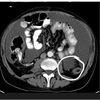

Q

A

1. Descending colon

2. Mesentery

How well did you know this?